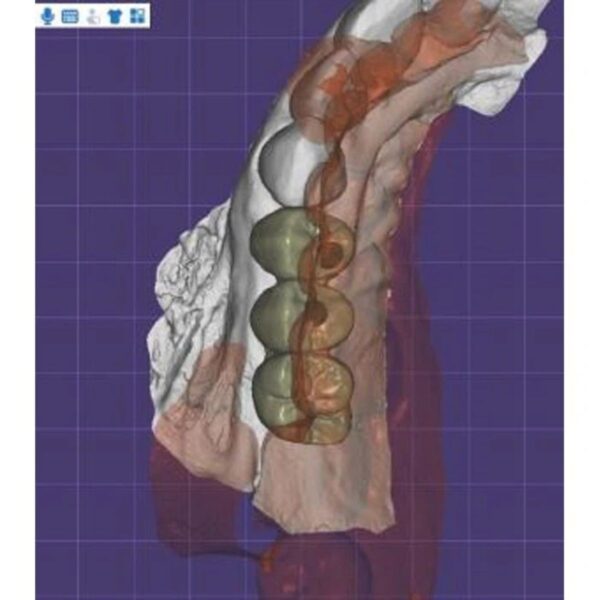

China Dental Design Complex Case Gallery

Challenging Projects That Showcase Our China Dental Design Expertise

Dental Crown Design

Implant Crown Design

- Full mouth rehabilitations

- Multi-unit implant bridges

- Aesthetic zone reconstructions

- Complex occlusal cases

- Surgical guide integration